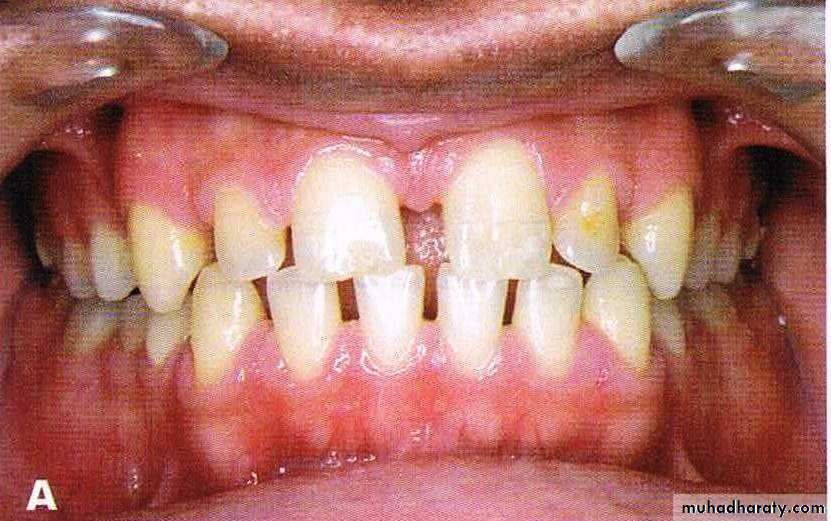

Bimaxillary protrusion

Bimaxillary proclination: the teeth are proclined on normal bases

Bimaxillary protrusion or bialveolar protrusion refers to a protrusive dentoalveolar position of maxillary and mandibular dental arches that produces aconvex facial profile .Bimaxillary prognathism: the jaws/basal bones are forward relative to the cranial base

Features

• Soft tissue• Convex facial form.

• Reduced lip length.

• Lips incompetency.

• Low lower lip line and high upper lip line

• prominent lips.

• Receded chin.

• Dental

• Dental bimaxillary proclination• Larger dental arch length with resultant spacing and diastema

• Normal or increased OJ

• Variable molar relationship but usually normal.

• Large teeth compared to normal population

• May have other superimposed malocclusion